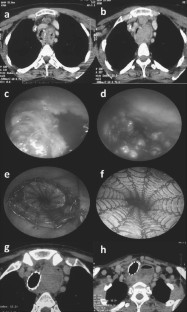

Fig. 1

Fig. 2

Fig. 3

Fig. 4